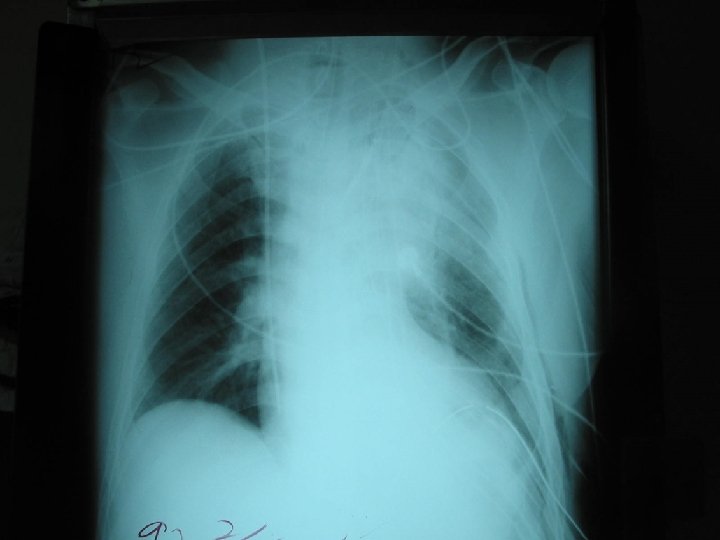

Case w 55 y/o male, HTN for 20+ years with regular medical control for 5 years w Chronic dissecting aortic aneurysm type III noted for 5 years w Left chest pain for 1 week w Denied other systemic diseases w Laboratory data: within normal range

Case w Normal screening spirometry w 2 -D echocardiography: dilated aortic root(diameter 63 mm) & LA, mild MR, good LV contractility w Planning: 1. Left post-lat thoracotomy 2. Femoralfemoral CPB 3. Hypothermia with circulation arrest and retrograde cerebral perfusion via high CVP 18~20 mm. Hg by femoral artery perfusion and partial clamp of venous drain tube 4. Restore proximal aorta perfusion after proximal anastomosis through graft cannulation 5. Open distal anastomosis